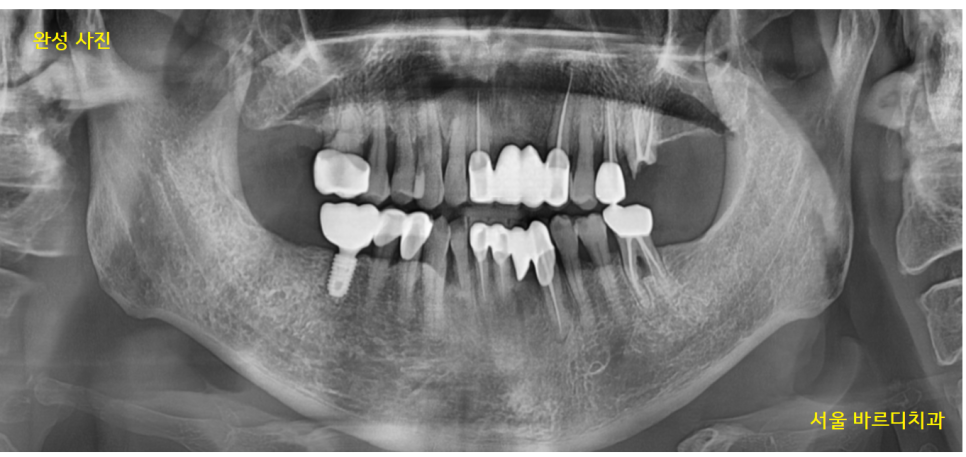

2021.09.28

수술 후 3개월 뒤 뼈와 임플란트가 잘 붙어서

보철을 완성해 드렸습니다.

23.08.07

고덕역 임플란트 완성 사진입니다.